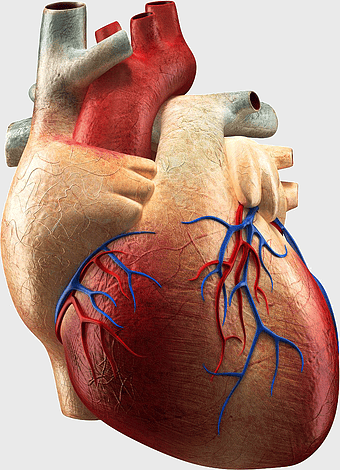

heart anatomy, cardiovascular health, drug therapy for heart disease, FDA approved heart medications, human heart model, medical illustration of heart, cardiology treatment options -